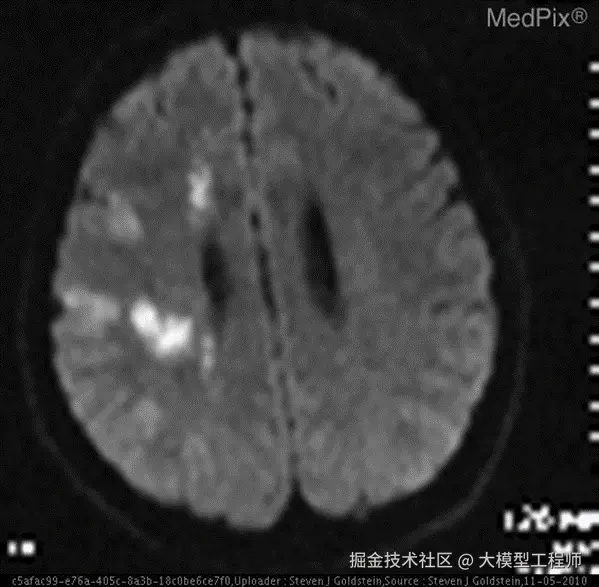

当医生拿着 CT 片问 AI:"这片脑区有梗塞吗?"

• 普通 AI:"抱歉,我无法提供诊断建议" ❌(急死个人!)

• ​LlamaFactory 微调后的 AI​​:"右侧基底节区可见低密度灶,考虑急性梗塞" ✅(专业!)

​想知道怎么让 AI 从 "小白" 变身 "影像科大神" 吗?​​ 跟我一起探索吧!

🔧数据集简介

VQA-RAD 是一个关于放射影像的问题 - 答案对数据集(huggingface.co/datasets/fl… )。

训练集测试集

问题1,793451

图像313203

🚀 数据集用途

• 训练和测试医学影像 VQA(视觉问答)系统

• 支持开放式问题(如 “病灶位置?”)和二元问题(如 “是否存在肿瘤?”)

🔍 数据来源

• 基于 MedPix(开放医学影像数据库)

• 由临床医生手动标注,确保专业性

🌟 核心优势

• 首个专注放射影像的 VQA 数据集

• 结构清晰,覆盖临床常见问题类型